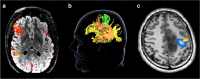

Diffuse gliomas are infiltrative primary brain tumors with a poor prognosis despite multimodal treatment. Maximum safe resection is recommended whenever feasible. The extent of resection (EOR) is positively correlated with survival. Identification of glioma tissue during surgery is difficult due to its diffuse nature. Therefore, glioma resection is imaging-guided, making the choice for imaging technique an important aspect of glioma surgery. The current standard for resection guidance in non-enhancing gliomas is T2 weighted or T2w-fluid attenuation inversion recovery magnetic resonance imaging (MRI), and in enhancing gliomas T1-weighted MRI with a gadolinium-based contrast agent. Other MRI sequences, like magnetic resonance spectroscopy, imaging modalities, such as positron emission tomography, as well as intraoperative imaging techniques, including the use of fluorescence, are also available for the guidance of glioma resection. The neurosurgeon's goal is to find the balance between maximizing the EOR and preserving brain functions since surgery-induced neurological deficits result in lower quality of life and shortened survival. This requires localization of important brain functions and white matter tracts to aid the pre-operative planning and surgical decision-making. Visualization of brain functions and white matter tracts is possible with functional MRI, diffusion tensor imaging, magnetoencephalography, and navigated transcranial magnetic stimulation. In this review, we discuss the current available imaging techniques for the guidance of glioma resection and the localization of brain functions and white matter tracts.